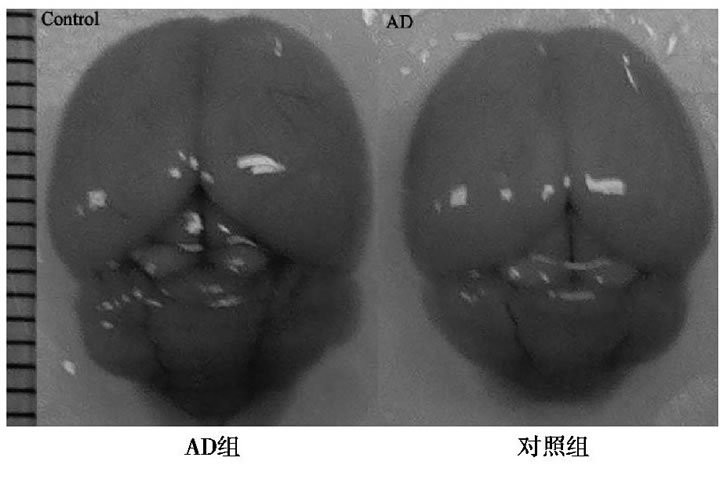

2.1 AD和對(duì)照組全腦圖

與對(duì)照組比較, AD小鼠完整腦組織表面泛白、無(wú)血色, 血管明顯減少, 表明D-半乳糖聯(lián)合三氯化鋁已經(jīng)對(duì)小鼠的腦組織形成退行性損傷。見(jiàn)圖1。

圖1 AD組和對(duì)照組小鼠全腦圖